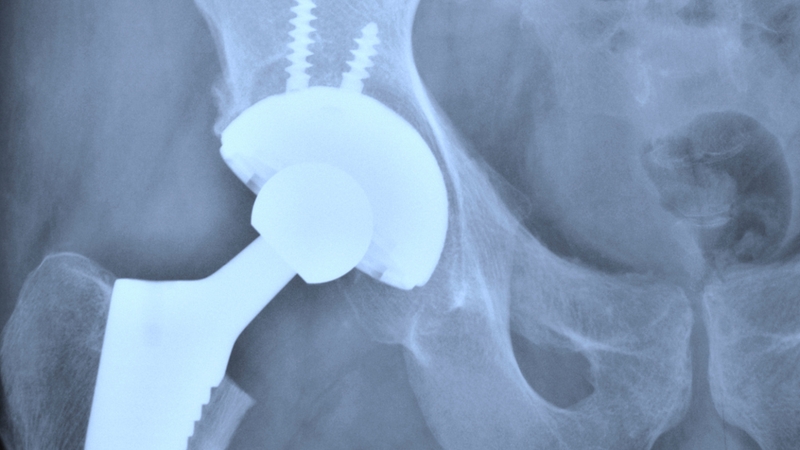

Lisburn-based Cirdan Imaging manufactures and distributes software and imaging solutions for the acceleration and enhancement of medical diagnosis. It was established in 2010.